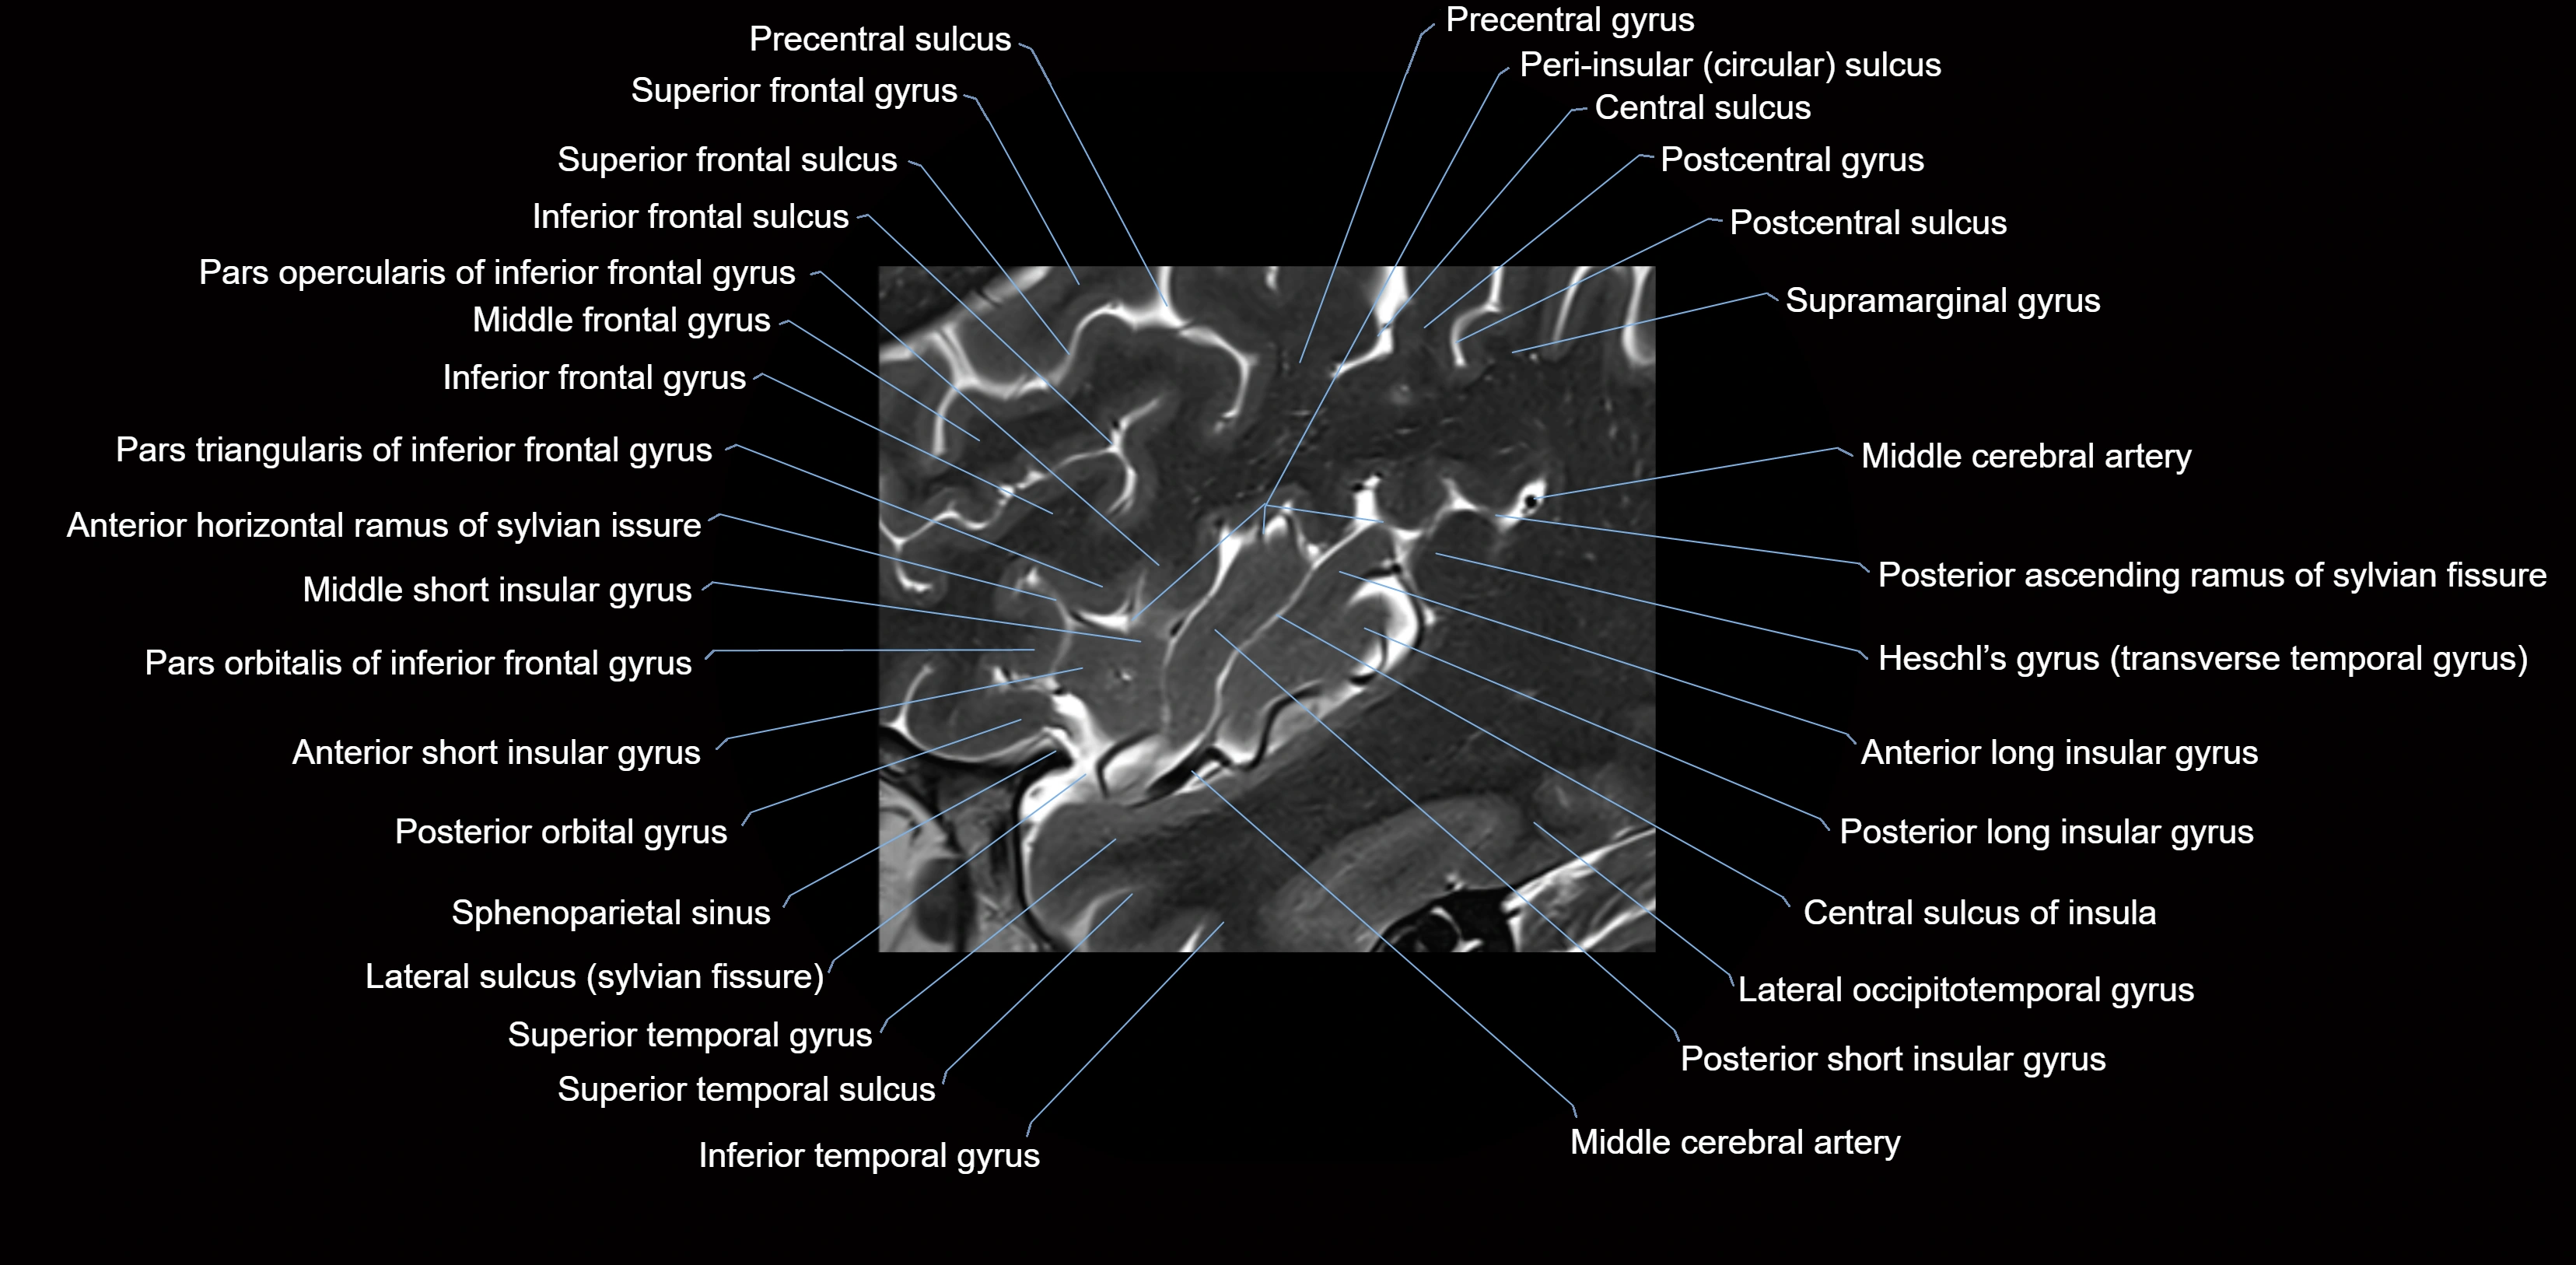

The anterior ascending ramus of the Sylvian fissure is a significant anatomical landmark in the lateral surface of the cerebral hemisphere. It represents one of the key branches of the Sylvian fissure (also known as the lateral sulcus) and plays an essential role in demarcating the boundaries between important cortical regions, notably within the frontal and parietal lobes. Understanding its anatomy and imaging appearance is crucial in neuroradiology, neurosurgery, and neuroanatomy for accurate localization and identification of adjacent brain structures.

• The anterior ascending ramus is a short, superiorly oriented branch that arises from the main stem of the Sylvian fissure.

• It projects upward (anteriorly and slightly dorsally) from the lateral sulcus into the inferior frontal gyrus.

• This ramus separates the pars opercularis (opercular part) from the pars triangularis (triangular part) of the inferior frontal gyrus.

• The anterior ascending ramus marks the boundary between Broca's area and adjacent cortical areas in the dominant hemisphere.

• Serves as an anatomical landmark for neurosurgical planning and neuroimaging.

• Helps define Broca’s area (important for speech production) in the dominant hemisphere.

• Aids in the localization of cortical regions during functional mapping and epilepsy surgery.

MRI Appearance

• T1-weighted imaging:

• The Sylvian fissure and its anterior ascending ramus appear as low-signal intensity (dark) CSF-filled clefts between the gyri.

• Clear demarcation between adjacent gray and white matter.

• T2-weighted imaging:

• The fissure, including the anterior ascending ramus, is hyperintense (bright) due to CSF signal.

• Better visualization of the separation between opercular and triangular parts of the inferior frontal gyrus.

• FLAIR imaging:

• The ramus is visualized as a linear dark space (suppressed CSF signal) between the surrounding cortex.

• Adjacent cortical and subcortical abnormalities (e.g., edema or gliosis) can be assessed relative to the ramus.